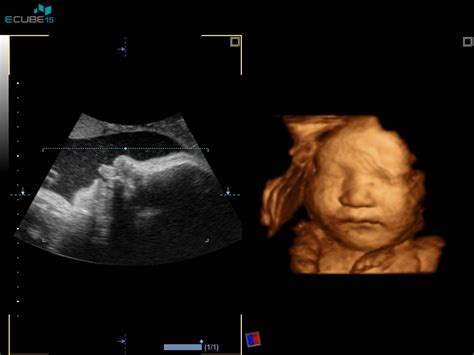

- Nezaveden spontani splav: Nosečnost je izgubljena, vendar ženska morda ne zazna simptomov. Ultrazvok potrdi, da plod nima srčnega utripa.

- Popoln splav: Maternična votlina je po izgubi nosečnosti prazna, saj je ženska krvavela in izločila fetalno tkivo. Ultrazvok potrdi, da je maternična votlina popolnoma prazna.